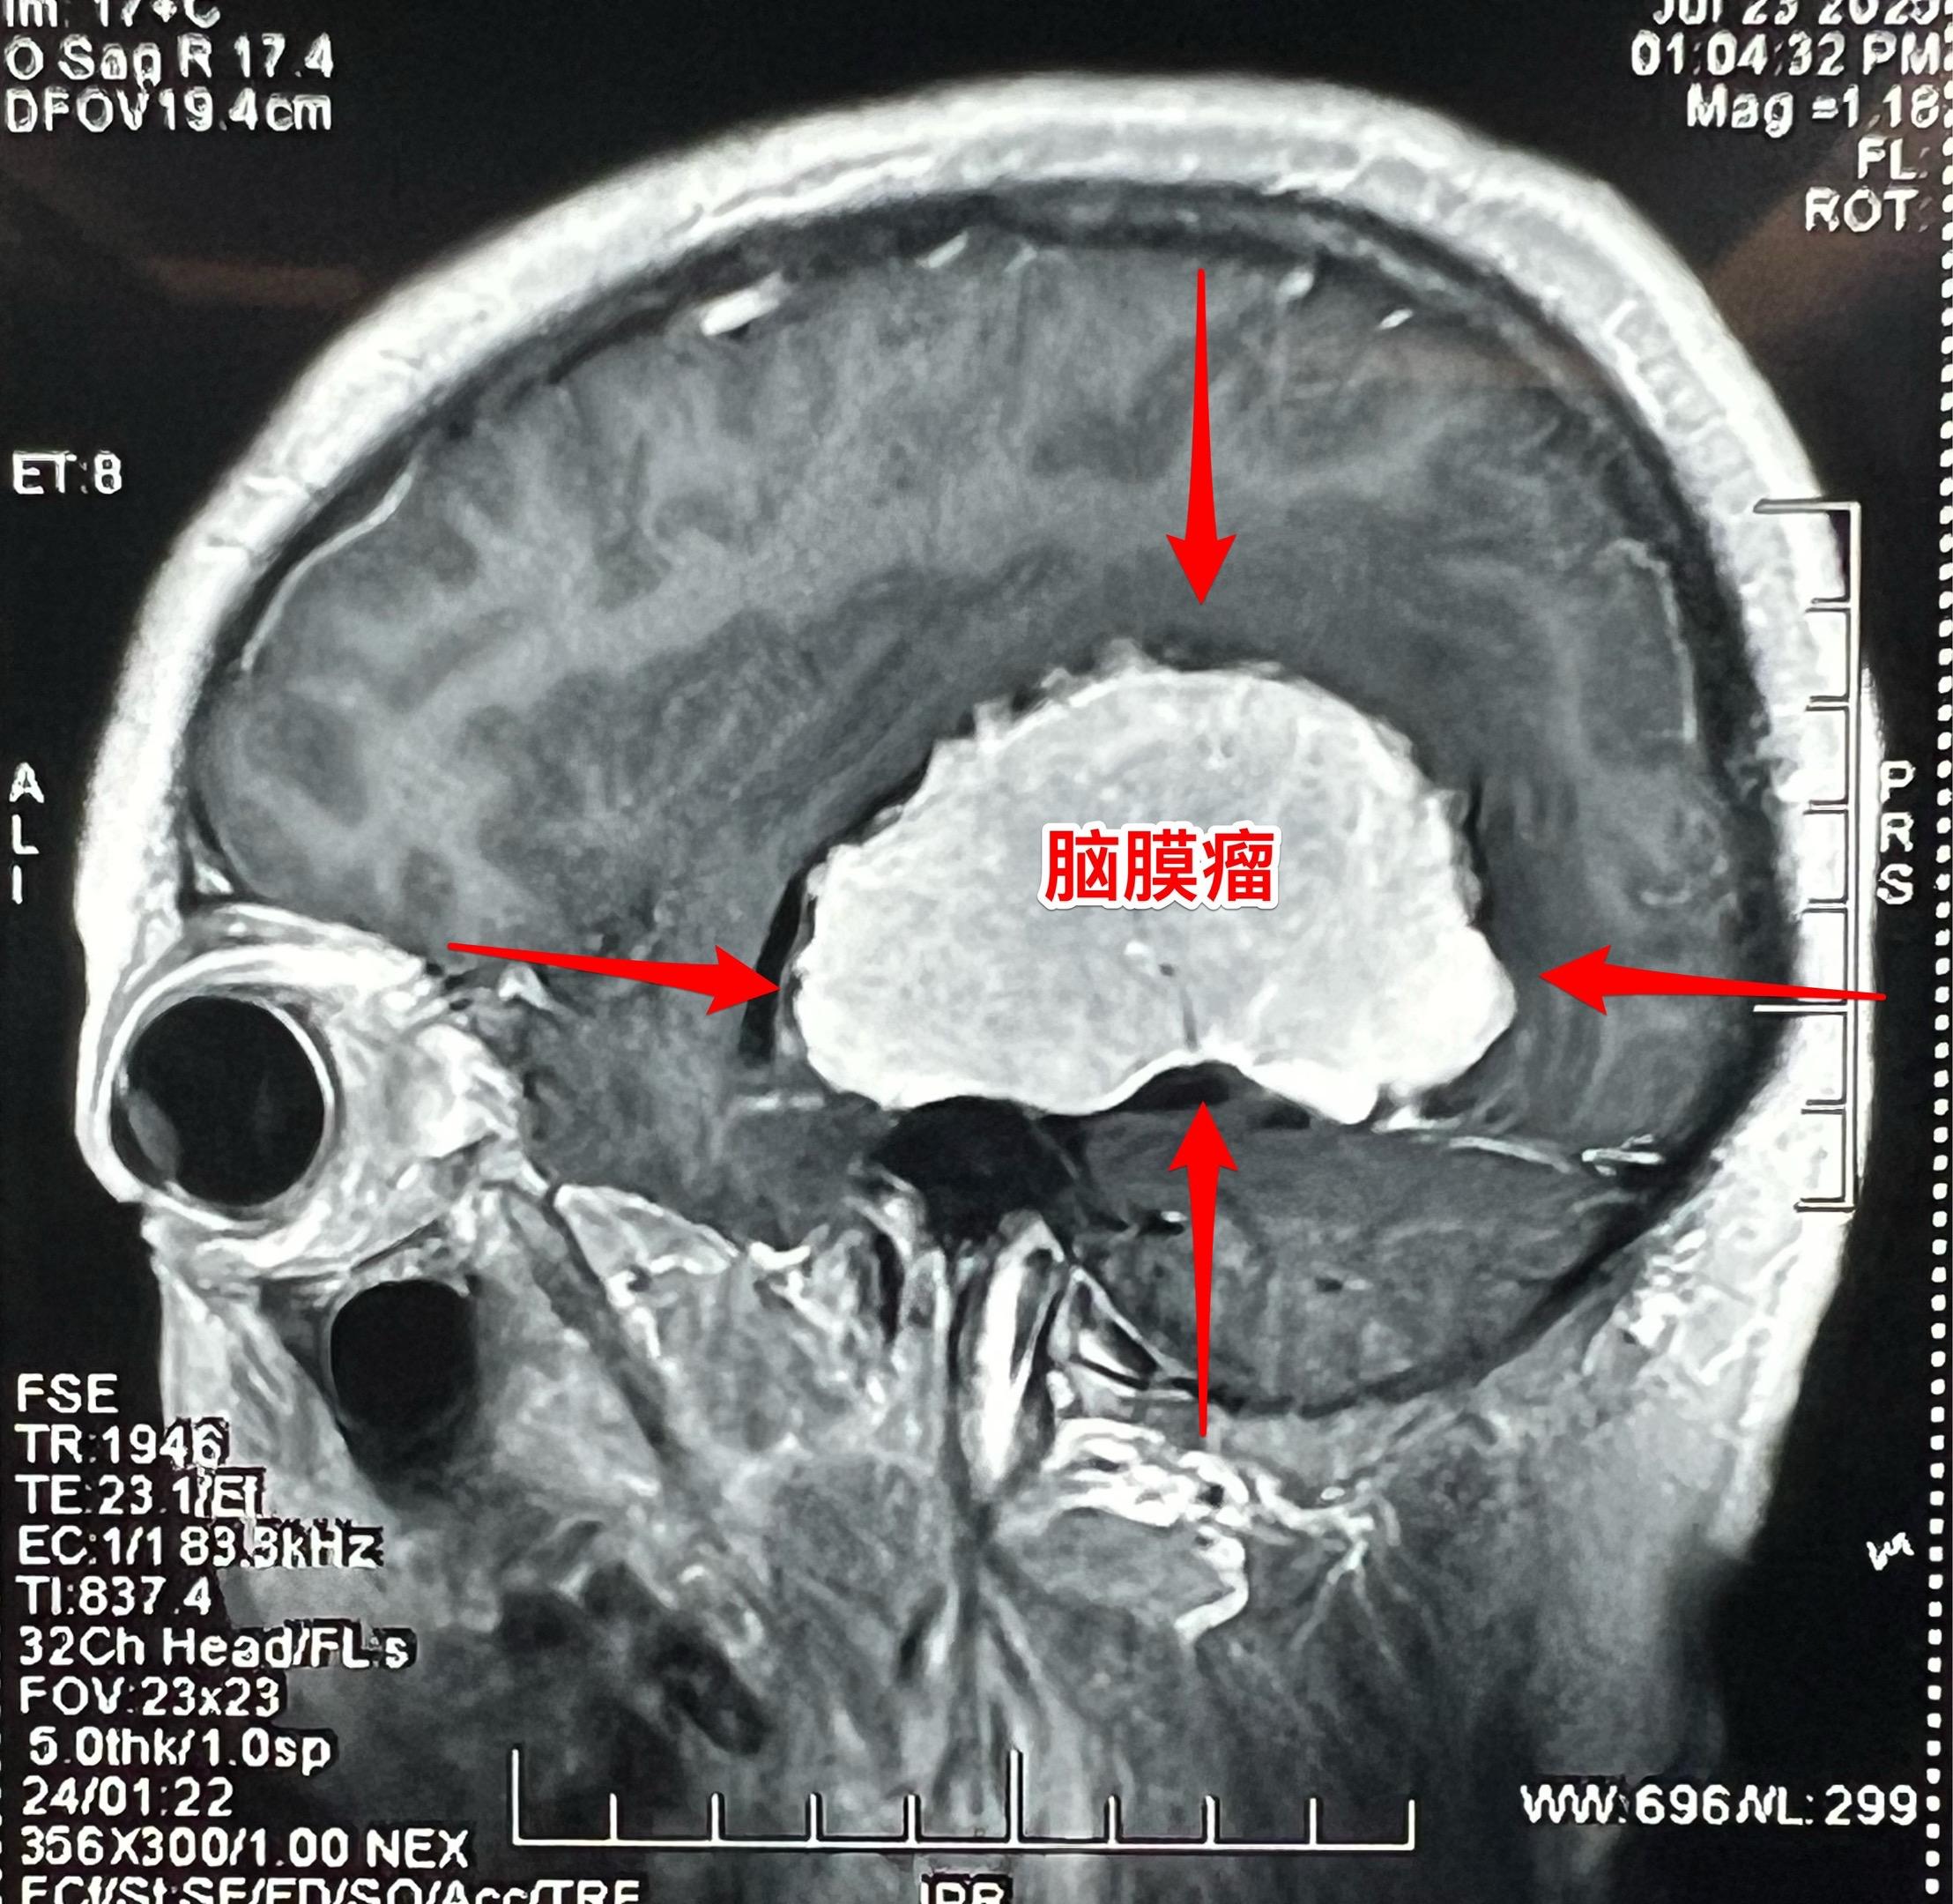

藏族牧民脑肿瘤被发现时像鸡蛋一样大。青海省黄南州藏族牧民,43岁,女性,平时以放养牦牛为生,家里有一百多头牦牛,她夫妻二人完全不能说汉语。 她头痛五年了,视力下降一年,迟迟没有就医,今年七月份因视力很差了才到西医医院检查,发现病根儿是脑膜瘤。如图所示,脑膜瘤像鸡蛋一样大。 发现脑肿瘤后,他们第一步是找活佛预判凶吉,指导治疗方向! 2025年8月1日作了手术,将肿瘤完全切除。希望她能顺利出院!